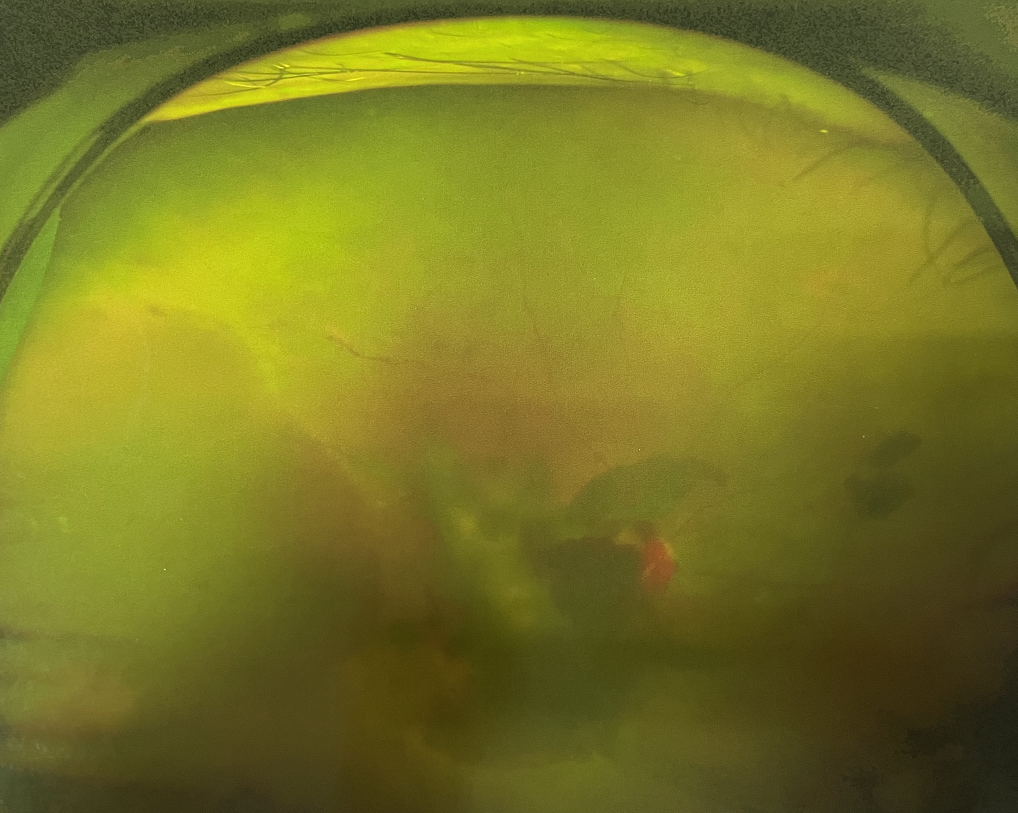

右眼術(shù)前

眼底病專科張小虎醫(yī)生檢查后,診斷王女士為“雙眼玻璃體積血、雙眼糖尿病視網(wǎng)膜病變V期”。(V期即5期,纖維增生期,出現(xiàn)纖維膜,可伴視網(wǎng)膜前出血或玻璃體出血。)

張小虎醫(yī)生為王女士進(jìn)行右眼玻璃體腔注藥術(shù),3天后進(jìn)行右眼23G玻璃體切割術(shù)后視力有所提升。

4個月后王女士來院取硅油,取油后視力恢復(fù)到0.6。“當(dāng)時來的時候真的只能看到模糊的影子,特別害怕覺得完了,想說眼睛估計(jì)要瞎了,沒想到手術(shù)后視力竟然提升了,現(xiàn)在也看得比較清楚了。”王女士說到。

張小虎醫(yī)生表示,糖網(wǎng)病進(jìn)展到嚴(yán)重增殖期帶來的視力損傷往往是極其嚴(yán)重的,目前王女士右眼從術(shù)前0.02恢復(fù)到術(shù)后0.6,已屬十分難得。